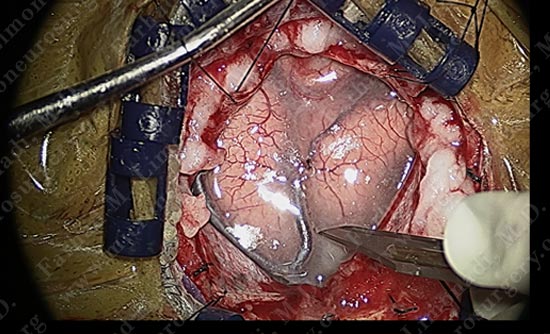

While patient is awake and conversing with Dr. Limonadi, motor cortex stimulation was utilized to locate the motor cortex.

Motor cortex was identified and is colored green. The tumor is deep and within the parenchyma of this gyrus.